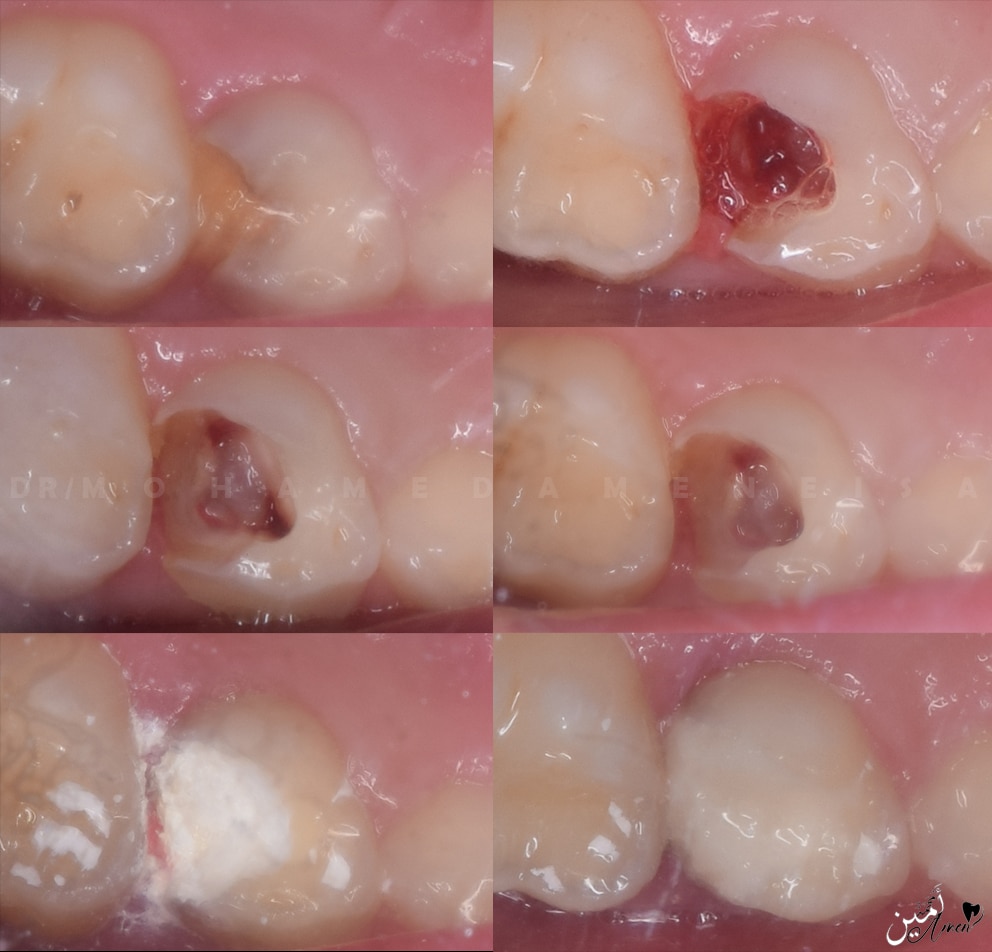

- Starting open access with large round bur to feel with the drop and to avoid perforation in the pulpal floor, after the drop you start deroofing, You can use endo Z bur here, and you can complete with large round bur.

- You should do complete deroofing to locate the canals..

- After completely deroofing, start to remove the coronal pulp tissue with a large round bur or sharp excavator, but it is preferable to use a sharp excavator to avoid perforation

- Remove all coronal inflamed pulp tissue, especially above the canals, to remove all inflamed pulp tissue.

- Stop bleeding and achieve hemostasis by using cotton pellet with saline in the cavity for 5 minutes

- If bleeding has stopped, it is indication that the inflammation is constricted to coronal pulp tissue and go to pulpotomy, If not stop, you have two possibilities: